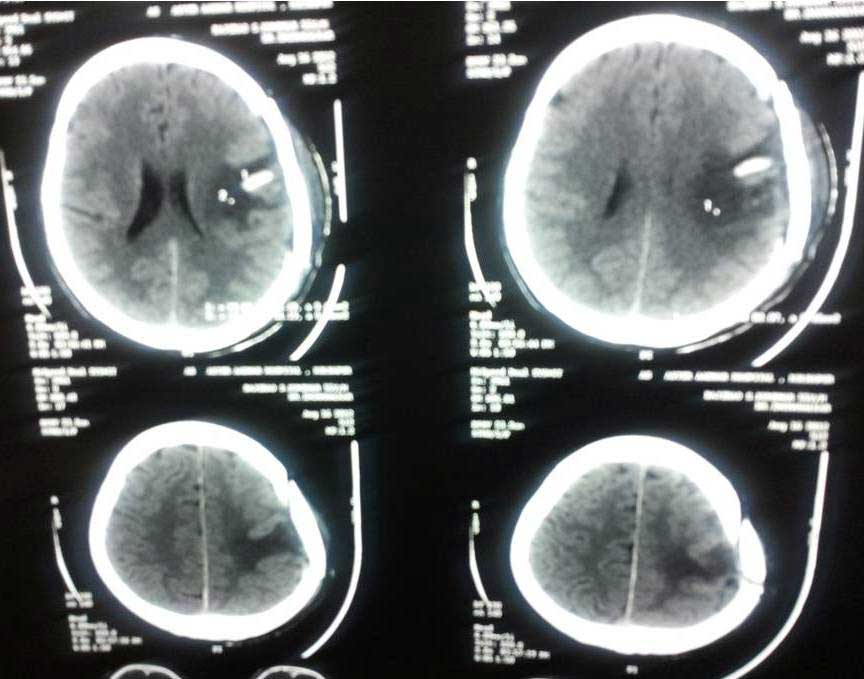

Brain Abscess Brain Abscess Post OP 2 Clinical Intra OP ,After Excising The Granuloma Intaop Scalp Abscess CT Scalp Abscess Cerebellar Abscess Post OP Clinical Cerebellar Abscess Brain TB Granuloma Post OP CT Scan Brain Infection Brain Abscess Preop MRI 2 Brain Abscess PRE OP Clinical 1 Brain Abscess PRE OP Brain Abscess Intraop 2 Brain Abscess Following Shunt Temporal Abscess T2W of TB Granuloma Scalp Abscess Preop CT Marking PRW OP MRI of TB Granuloma Post OP Clinical Photo Post OP Cerebellar Abscess Post OP Brain Abscess Intraop Specimen of Granuloma